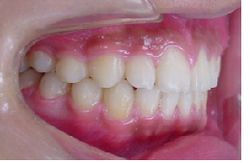

当矯正歯科医院では非抜歯で治療をしています。

治療後の後戻りが矯正では問題となりますが歯を抜かないで治療しているため、後戻りも最小限で済みます。

初診時

終了時

術後3年後

術後4年後